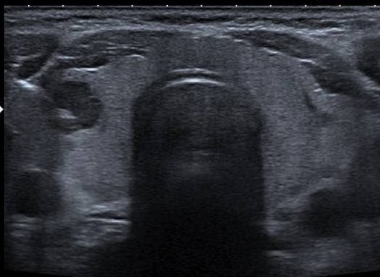

Cet examen permet de réaliser un prélèvement d’un ou de plusieurs nodules thyroïdiens sous guidage et contrôle échographique.